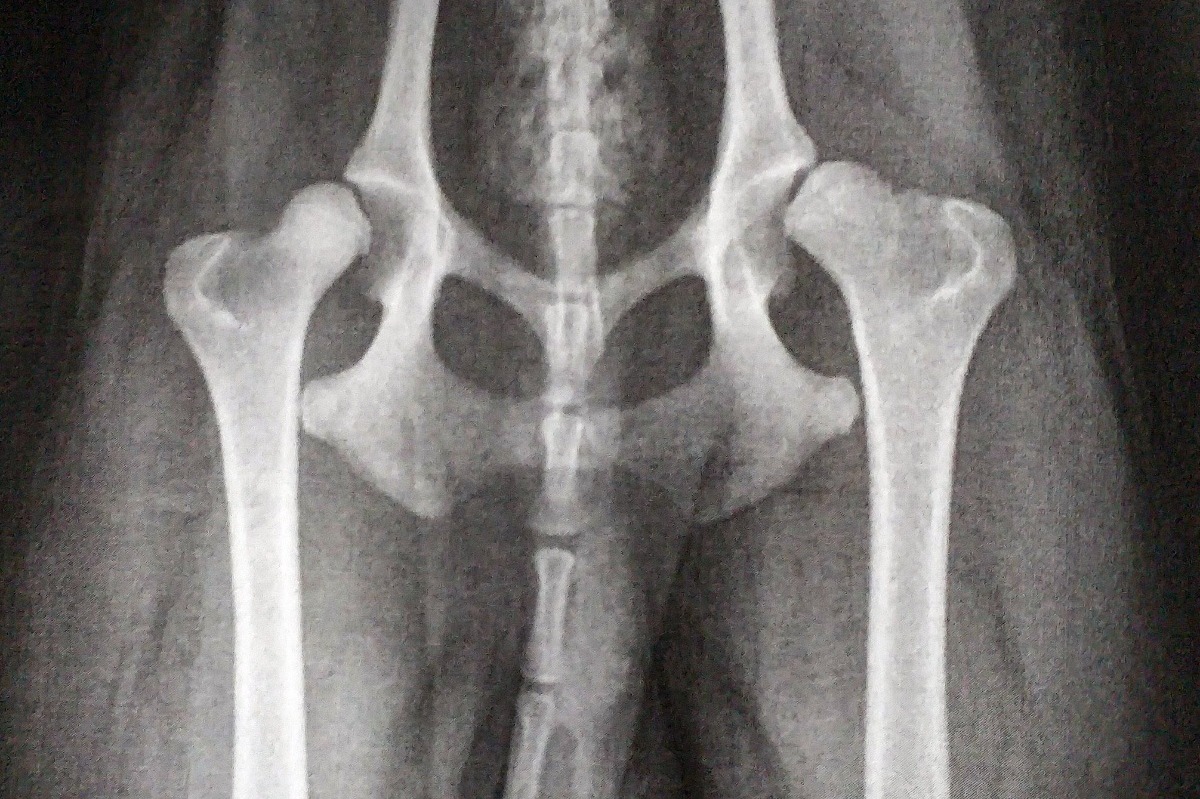

The result was the following picture. The second xray picture is how the hip bones SHOULD be aligned to the hip sockets. We were told that Haku SHOULD NOT be able to walk. That the only reason he can literally stand and walk is because of us building up his muscles very well from when we got him.

Haku has something called hip dysplasia, and a severe version at that. To fix this, the proposed surgery they will have to cut off a part of his hip bone, and attatch a prostethic part which would work as an interim between the hip bone and the hip socket, linking them together the way they should be. This is the procedure that has not only the most success rate, but also with the best outcome after rehabilitation for Haku.

To explain the insurance situation a bit more: Basically to do the surgery we want, because it is the best one for Haku, they would have to first cut off a part of the hip bone - something called "caput resection" (kaputresektion in swedish), and then attatch the prostethics. If we choose to do only the caput resection, which is a "viable" option (but much worse for the dog, and would most likely need to do surgery again later in his life), then the insurance company would pay for that. But if we choose to do the prosthethics part aswell, they say they will cover nothing because it falls under a different category of surgeries for them, which they apparently pay nothing for.